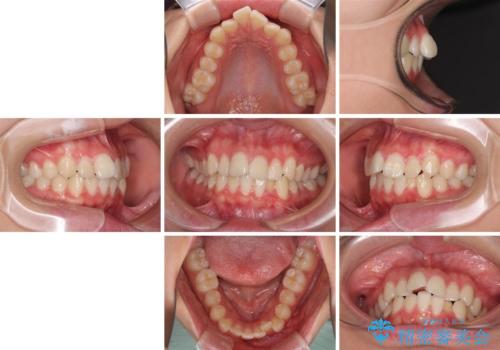

- 口元のデコボコを気にして来院された患者様です。

前歯の捻れにより口元が閉じにくくなっていたため、歯列全体の側方への拡大と、歯と歯の間を少し削ってスペースを獲得することとしました。

ゴムかけをしっかりと行ってもらい、スッキリとした口元に仕上げることができました。